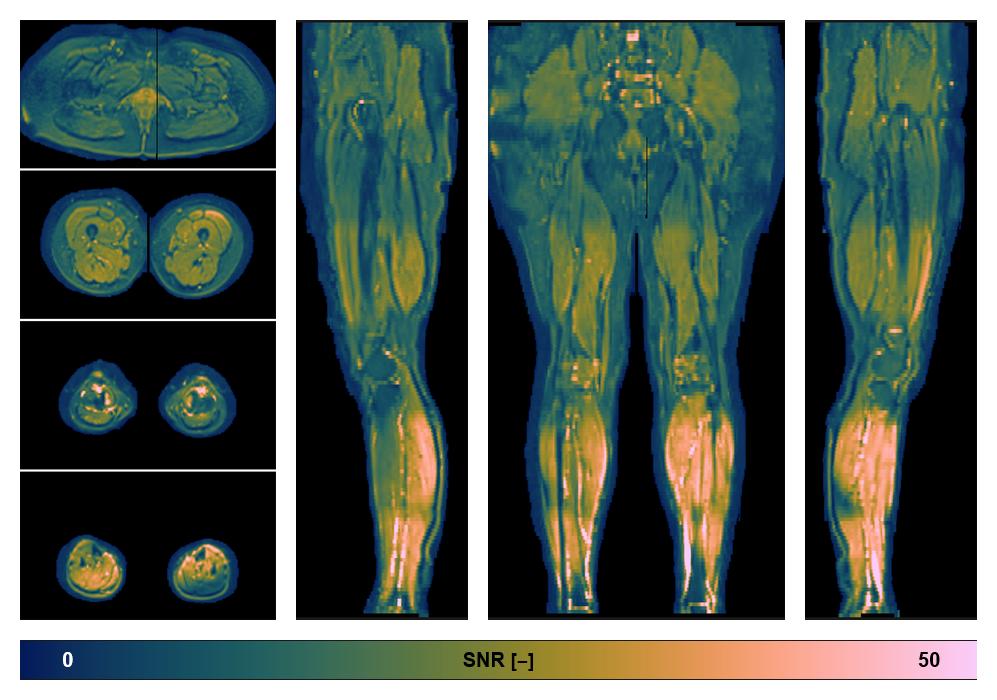

• SNR of the unweighted image

SNR distribution of the unweighted diffusion data.